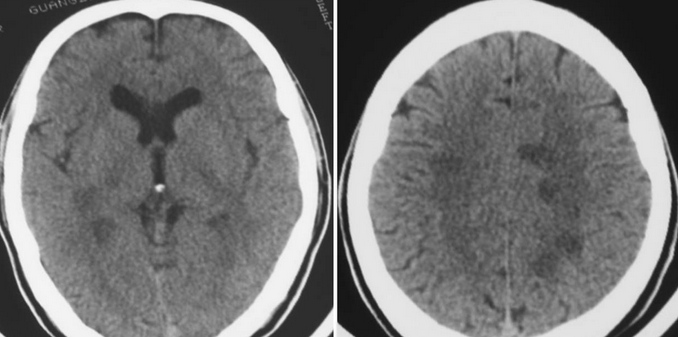

【辅助检查】行腰穿脑脊液检查除外"化脑"、"隐球菌性脑膜炎"等,头颅CT提示顶枕区小片低密度影,按"病脑"治疗后患儿精神状况及意识反应等好转,但体温未完全下降至正常,仍有37.5-38度的低热,

【诊疗经过】按"结脑"抗痨治疗3天后体温降至正常,但患儿出现夜休差以及极度烦躁不安等表现,因家属过分担忧抗痨药的"不良反应"而停止抗痨观察,烦躁未减轻,复查脑脊液提示白细胞数较高(3210/L),糖含量降低(2.89mmol/L[3.8---4.4]),头颅磁共振提示脑顶枕区皮层出现局限性片状信号灶。考虑"脑炎",结脑可能性仍大,再次抗痨治疗,总疗程约4周左右,抗痨过程中患儿仍间断烦躁,自主语言减少,同时出现渐进性认知障碍以及胡言乱语等表现。按"脱髓鞘性疾病"给于静点"人血丙种球蛋白"输注后患儿意识及精神反应等状况明显好转,复查脑脊液除糖稍低外其余均恢复正常,继续予以激素治疗。停用丙球后患儿意识及精神状况复又出现恶化,但总体水平仍较应用"丙球"前为好,复查头颅磁共振提示"脑白质病".出院后用药:强的松:7.5mg每日两次。每周减1片,直至减完鲁米那:早30mg.,晚15mg.,每周减半片,直至减完同笑:5ml.,每日两次.